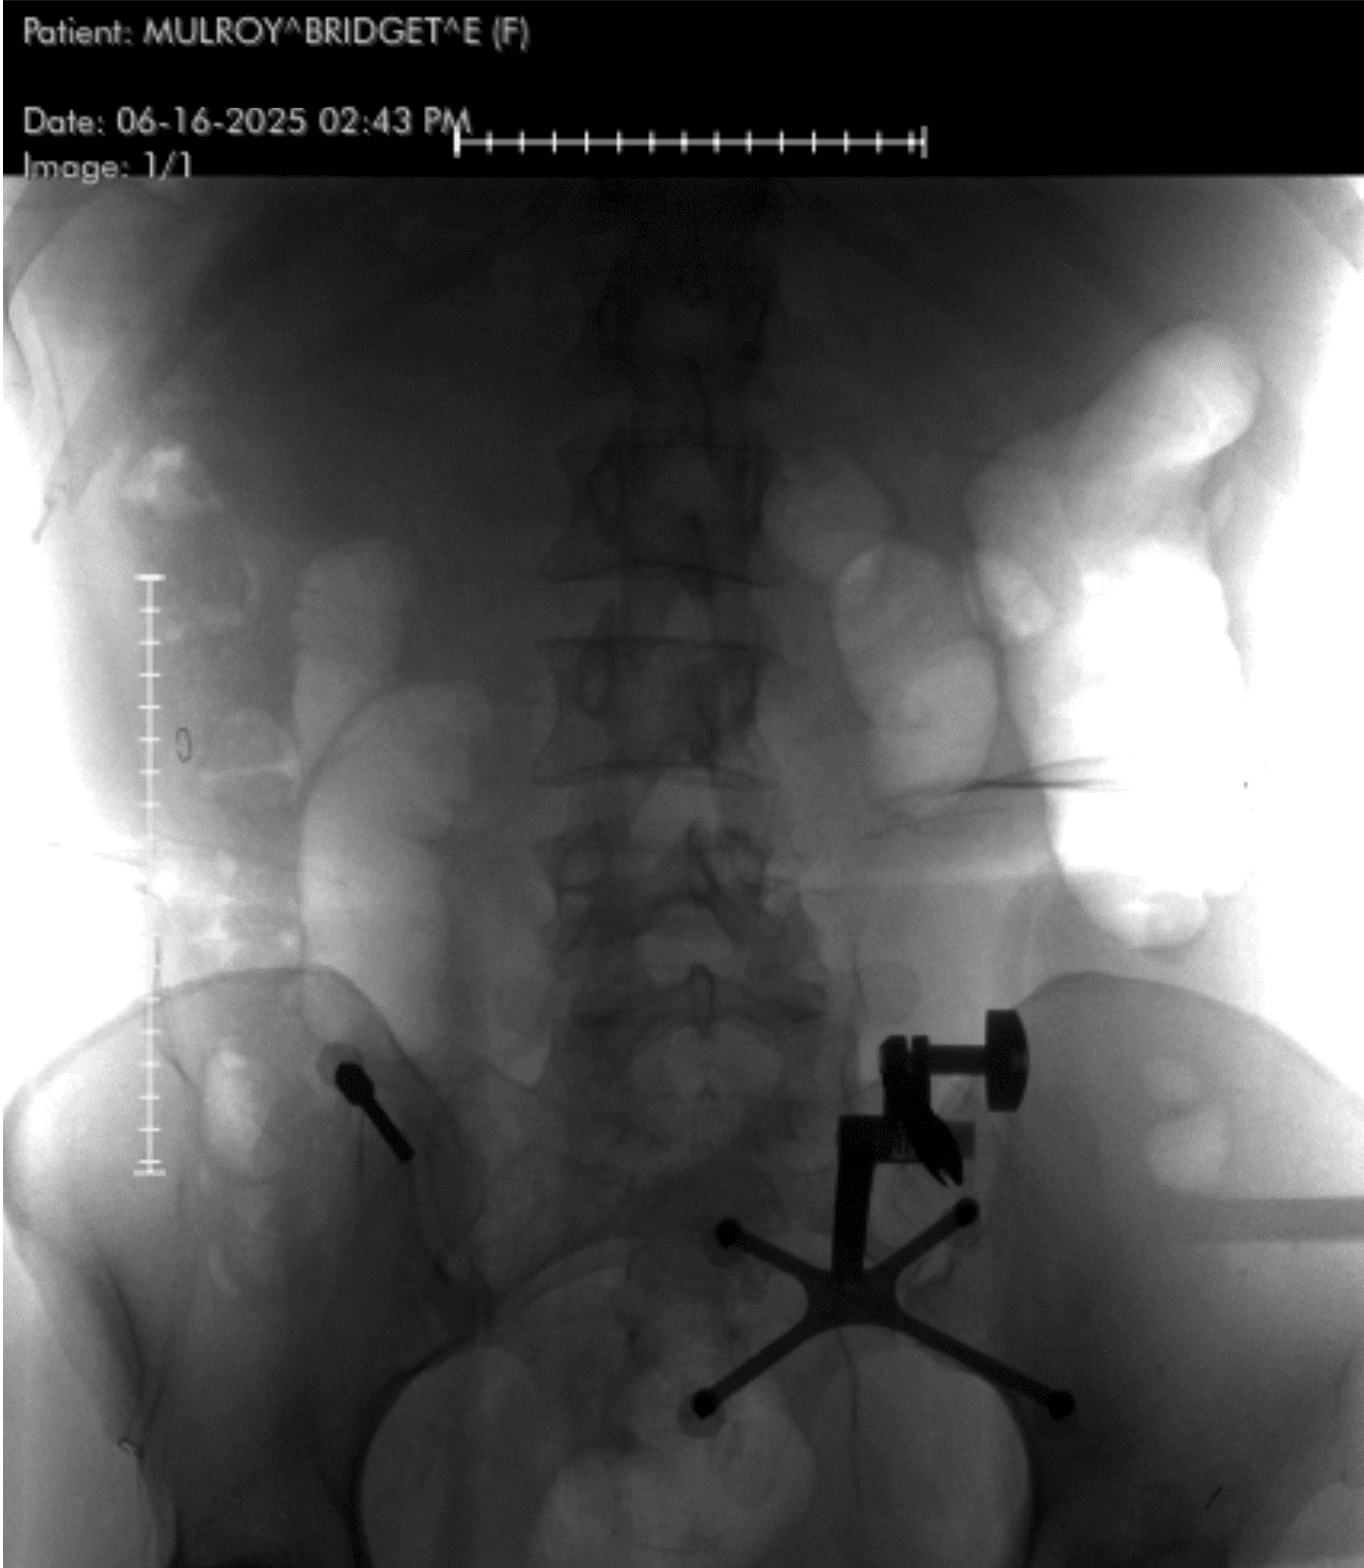

Picture Credit score: Bridget Mulroy

As an alternative of utilizing an exterior brace, Dr. Lopez used {hardware}—screws and rods—to create inner assist.

“Technically, you didn’t have a spinal fusion,” he clarified. “You had spinal instrumentation and stabilization. A fusion requires bone grafts and biologic processes to encourage new bone development.”

He carried out a minimally invasive posterior lumbar instrumentation from L2 to L5. Which means he made small incisions guided by real-time navigation utilizing a machine known as the O-arm—a rotating intraoperative CT scanner. A localizing pin in my pelvis communicated with a pc, which instructed him precisely the place to position every screw.

“As soon as the screws are inserted,” he defined, “I take advantage of an X-ray to position the rods. The important thing choices contain realizing which ranges to incorporate, guaranteeing screw trajectory is ideal, and having a plan if one thing doesn’t go proper.”

I requested him what turns into of all of the {hardware}—the screws, rods, and implants—as soon as the backbone heals.

“The method behind a posterior instrumentation with stabilization is as follows (I did this minimally invasive so it’s barely completely different): I positioned a steel localizing pin into your pelvis which talks to the pc within the room which helps us with actual time screw navigation. We spin a big machine known as an O-arm which performs in intraoperative CT scan which provides us loads of details about your bones. We use that as an actual time navigation for putting the screws into the bones. We then used a particular marker to know precisely the place to position your incisions based mostly on the real-time suggestions from the navigation (we are able to preserve the a number of incisions small due to this expertise). As soon as the incisions are made, we dissect down the pores and skin, fascia, muscle, and right down to the bones of the backbone. From there I take advantage of the real-time navigation to know the trajectory of the screw and place every one with a set of devices—first an axe to make a small gap within the bone, then a faucet to widen that gap a bit with the intention to higher facilitate screw insertion, then the precise screws. As soon as the screws are inserted, I take advantage of an x-ray machine to assist me place the rods. The actual determination making right here contains the pre-operative planning and realizing which ranges to incorporate, the right screw trajectory and to know if the suggestions from the reside navigation is correct, and what to do if a screw isn’t good.”